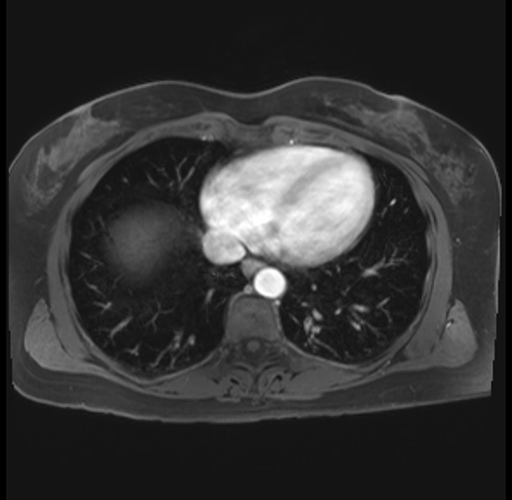

Imaging Analysis

Look through the patient's CT scan to identify any areas of concern for the necessary procedure.

Based on your CT findings, which issue(s) are present and would give reason for "planned slowing down moment(s)" in this case?

Considering a standard distal pancreatectomy procedure, what step(s) of the operation would you do differently in this case?